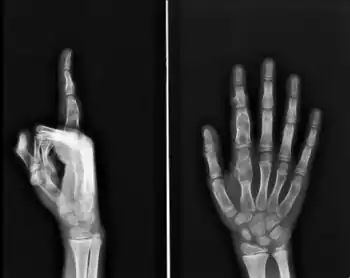

Maffucci syndrome -

X-ray wrist: Ollier disease in child -

X-ray hand:Ollier disease in child

Enchondromatosis is the presence of multiple enchondromas, occurring as part of Ollier disease, Maffucci syndrome, or metachondromatosis.[3] It has a tendency to affect short tubular bones of the hands and feet, but can occur in long bones, shoulder blades and hips.[3] It presents with bone deformity, lumps, or broken bone, typically in a child.[2]